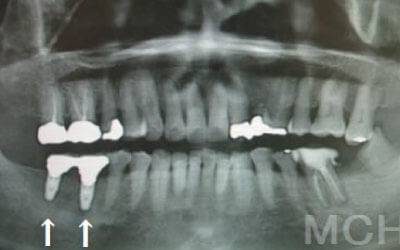

今回のご質問ですが、抜けた部分の骨が薄いなどの理由で「インプラントはできない」と言われた可能性があります。

前歯はもともと骨が薄く、歯が抜けると時間の経過とともにさらに骨が痩せてきてしまうので、インプラント治療の難易度が高い場所です。

ただ結論からお話すると、インプラント治療は可能です。

なぜなら、もし仮に骨が薄くても、骨の治療によって厚みが増せば、安全にインプラント治療が行えるからです。

なお、前歯のインプラント治療をご希望の方には、注意していただきたい点が4つほどあります。

1)インプラント治療を行う前に、骨の治療が必要かもしれません。

2)骨の治療から始めると、その分、治療期間が長くなります。

3)骨の治療は、通常のインプラント治療よりも難易度が高いため、経験の豊富な先生やインプラント認定医のいる歯科医院で治療を受けることをお勧めします。

4)骨の状況をしっかり把握するためにも、CT撮影が必須となります。